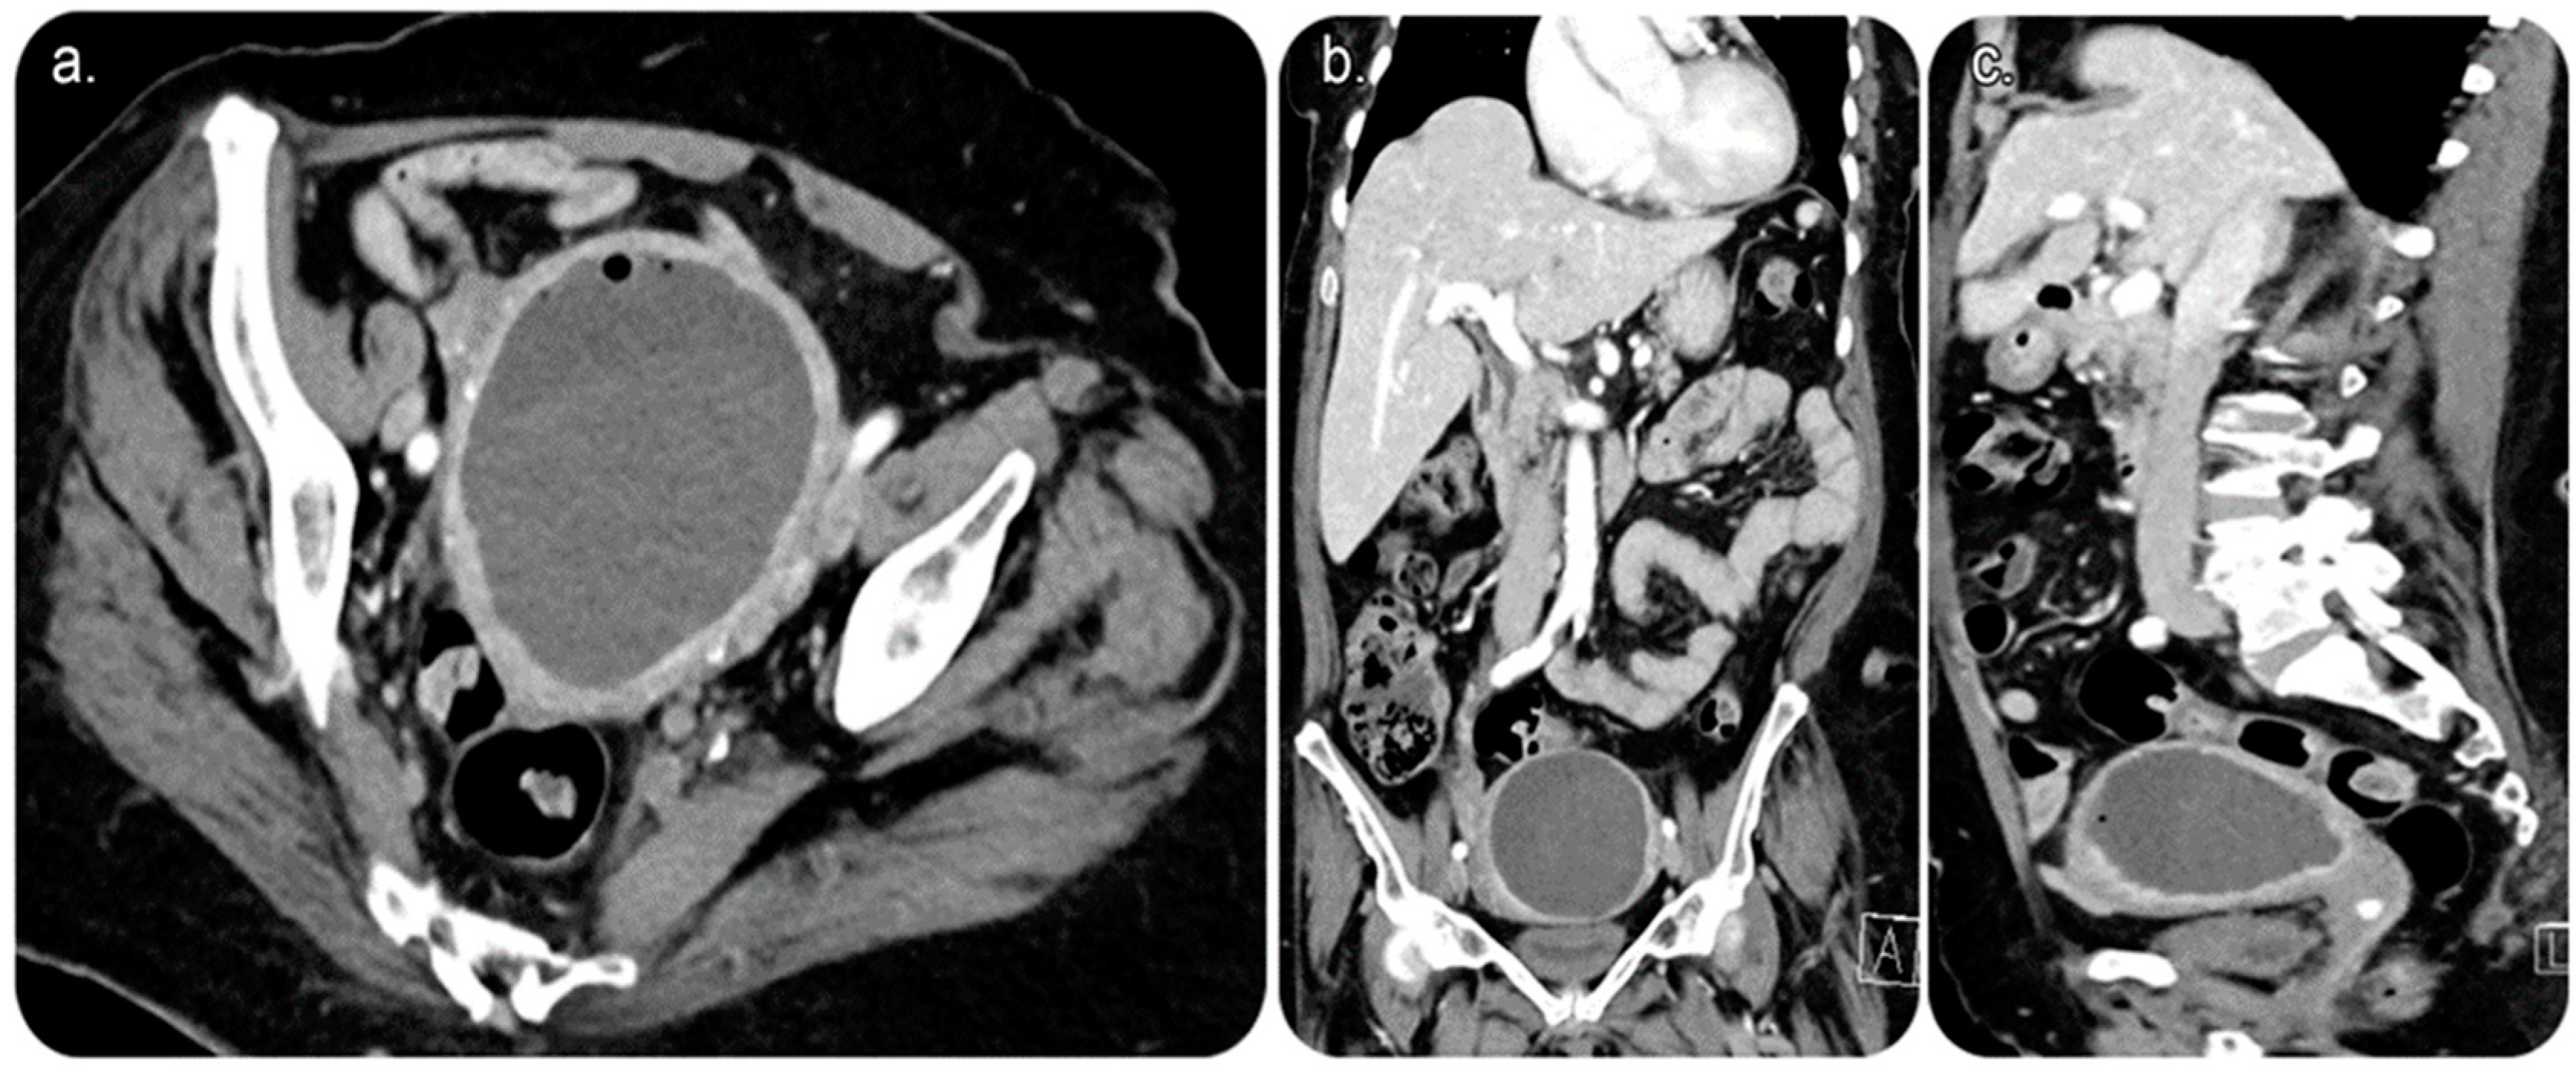

2. Case Presentation